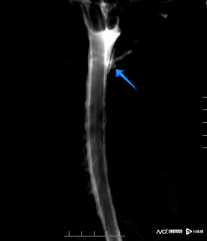

脑脊液水成像见颈2水平右侧脑脊液漏出;CTM脊髓造影见颈2水平右侧脑脊液漏出。

钟水生推断,可能是那次急刹车造成患者脊柱挥鞭样损伤,致脑脊液漏,引起低颅压综合征。